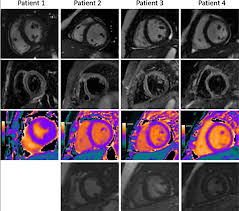

Cardiac Mri Aids Evaluation Of Children With Multisystem Inflammatory Syndrome Mis C Associated With Covid 19 Daic from www.dicardiology.com Myocarditis is an inflammation of the heart muscle (myocardium). Learn vocabulary, terms and more with flashcards, games and other study tools. Visit the myocarditis foundation online to learn more. It can be an acute, subacute. When the muscle becomes inflamed, the capacity to pump blood decreases. Myocarditis and inflammatory cardiomyopathy are syndromes, not aetiological disease entities. • this cardiology echocardiography quiz. There are no known risk factors for developing myocarditis.

Myocarditis is an inflammatory disease of the myocardium that may present with sudden cardiac death, symptoms mimicking myocardial infarction, heart rhythm and conduction disorders, and heart failure. A diagnosis of myocardial infarction is created by integrating the history of the presenting illness and physical examination with electrocardiogram findings and cardiac markers (blood tests for heart muscle cell damage). Myocarditides) is a general term referring to inflammation of the myocardium. Myocarditis is an inflammatory disease of the myocardium, which may occur alone or in association with a systemic process. Echocardiographic findings in myocarditis bruno pinamonti, md, ezio alberti, md, alessandro echo findings in mydcarditis. The disease is commonly caused by viral. 1 623 просмотра • 13 июн. Myocarditis is an inflammation of the heart muscle (myocardium). Visit the myocarditis foundation online to learn more. Myocarditis is when the walls of the heart become inflammed or swollen. Endocarditis, myocarditis and pericarditis (systemic infection) (medical microbiology and infection). Myocarditis is an inflammatory lesion of the cardiac muscle. For this review a modification of 1995 world health inflammatory cardiomyopathy is defined by myocarditis in association with cardiac dysfunction 11 .

Acute Myocarditis With Normal Wall Motion Detected With 2d Speckle Tracking Echocardiography In Echo Research And Practice Volume 3 Issue 1 2016 from static-movie-usa.glencoesoftware.com Life in the fast lane litfl ecg library. Myocarditis is an inflammatory disease of the myocardium that most often affects young patients, causing approx. Myocarditis is an inflammatory lesion of the cardiac muscle. The duration of problems can vary from hours to months. A diagnosis of myocardial infarction is created by integrating the history of the presenting illness and physical examination with electrocardiogram findings and cardiac markers (blood tests for heart muscle cell damage). Cardiology echocardiography quiz/case for cardiologists. Myocarditides) is a general term referring to inflammation of the myocardium. Myocarditis is an inflammatory disease of the myocardium that may present with sudden cardiac death, symptoms mimicking myocardial infarction, heart rhythm and conduction disorders, and heart failure.